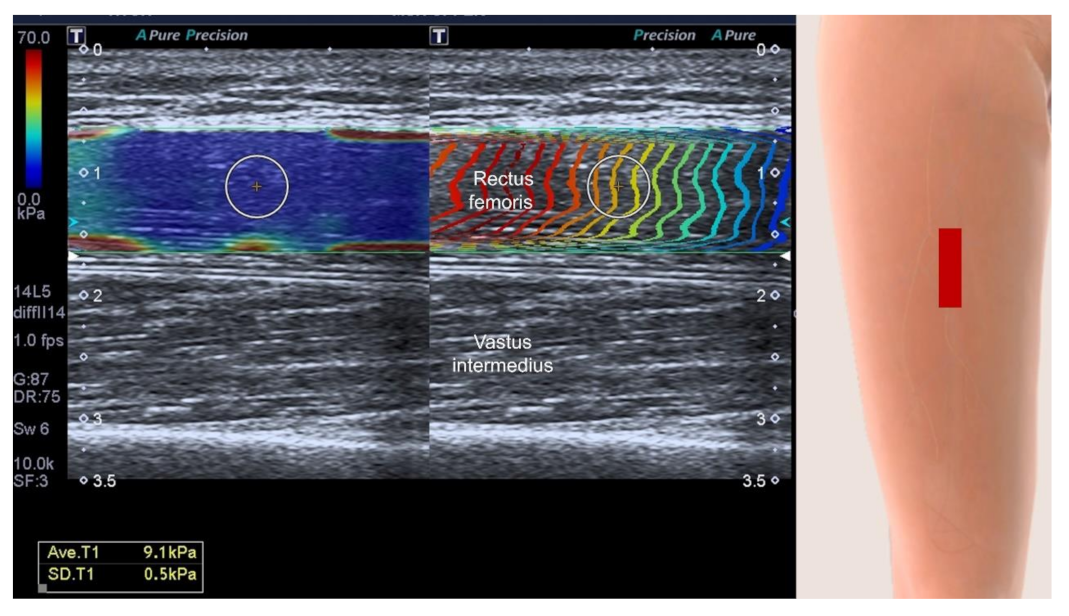

3.4.4. Muscle Stiffness Measurement by Sonoelastography

3.4.5. Contrast-Enhanced Assessment of Micro-Vascularity